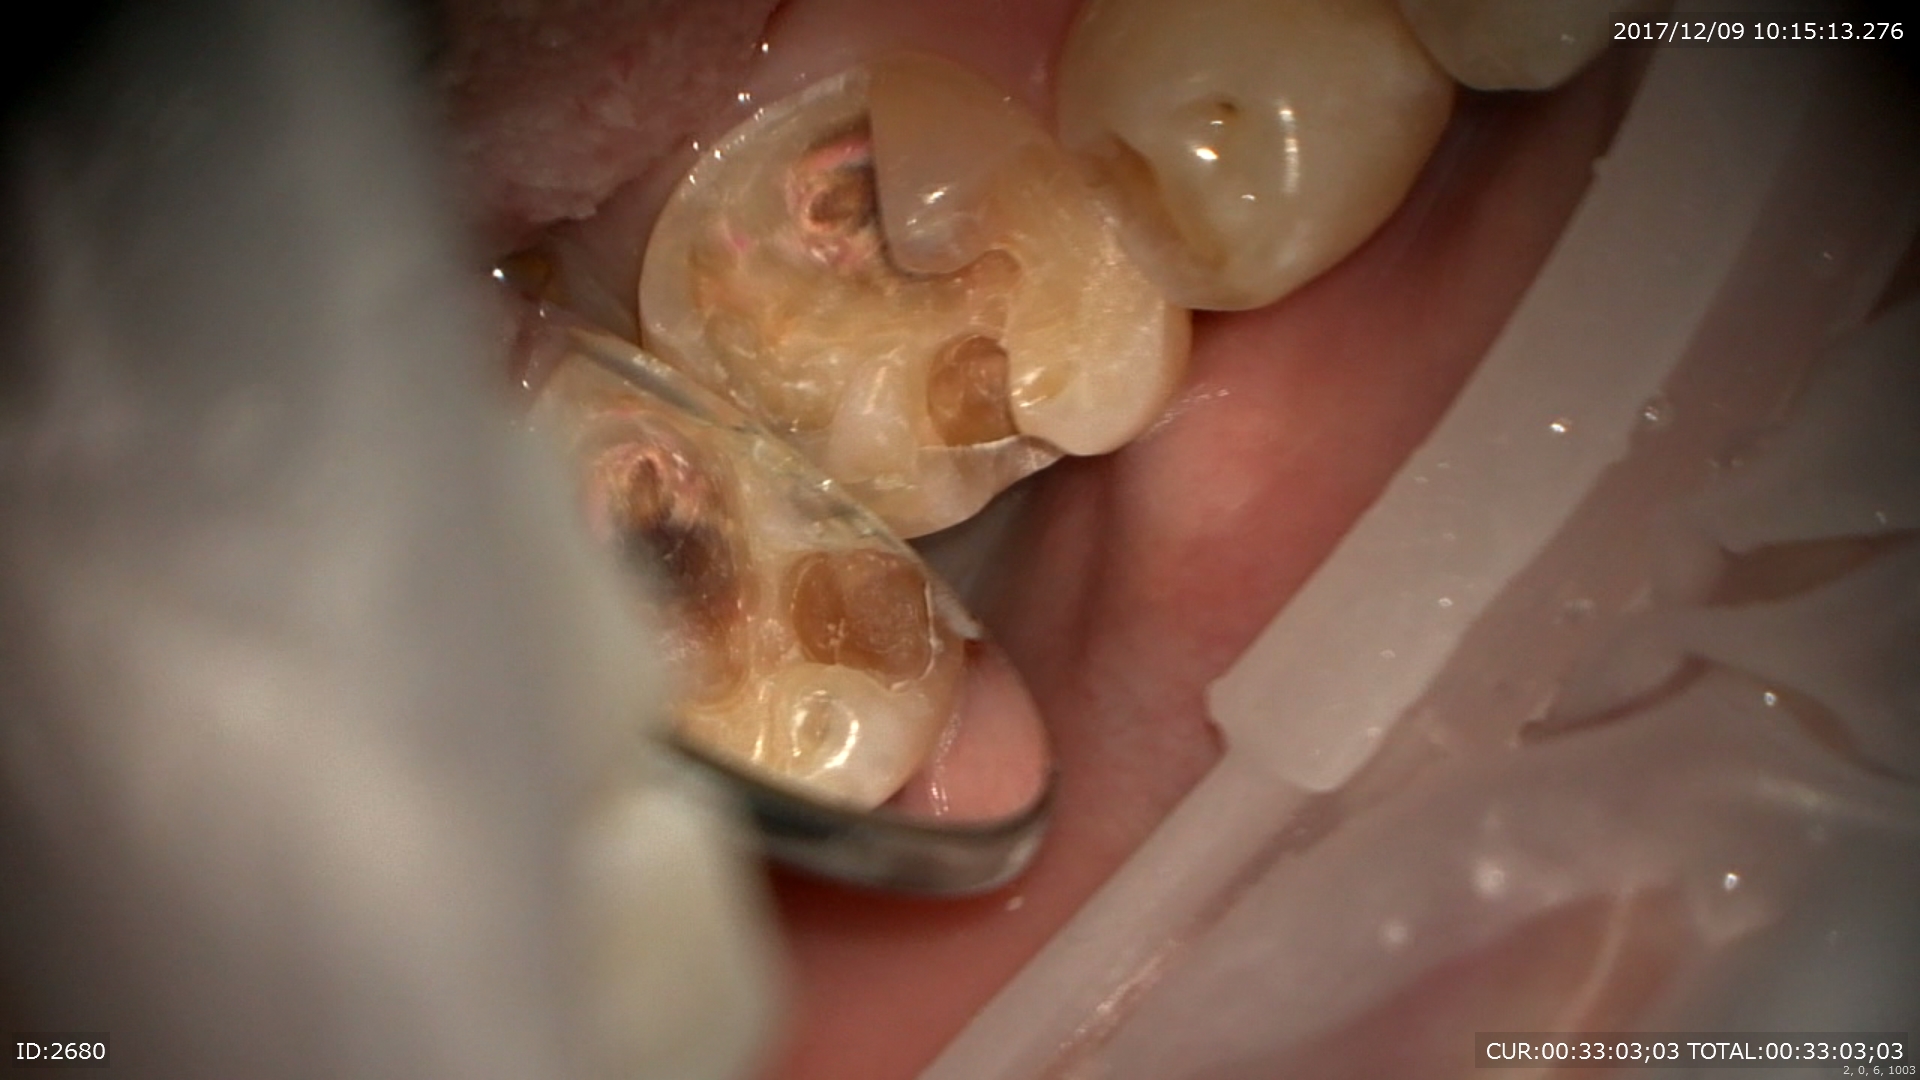

精密根管治療開始。8月。

やはり膿が!!感染源が。そして肝心の根管がやはりCTで見た通り狭窄。通らない。

約半年かけて本日を迎えました。6回目。

今日ダメだったらやめましょう。そう伝えCTを術前に撮影。

鼻の部屋の病気が引いていました!!嬉しい。治癒傾向は間違いがない。ただ治癒だけではだめだ。根治だと自分に言い聞かせ昼休みを使ってゆっくり丁寧にマイクロスコープで根管を探りました。

集中。

すると、、、開きました。ここか!!半年かかりました。

根尖見えますね。根管を綺麗にして。次回根充(MTA)予定です。時間がかかったけど本当に良かったです。お付き合いいただいたMさんに感謝!!